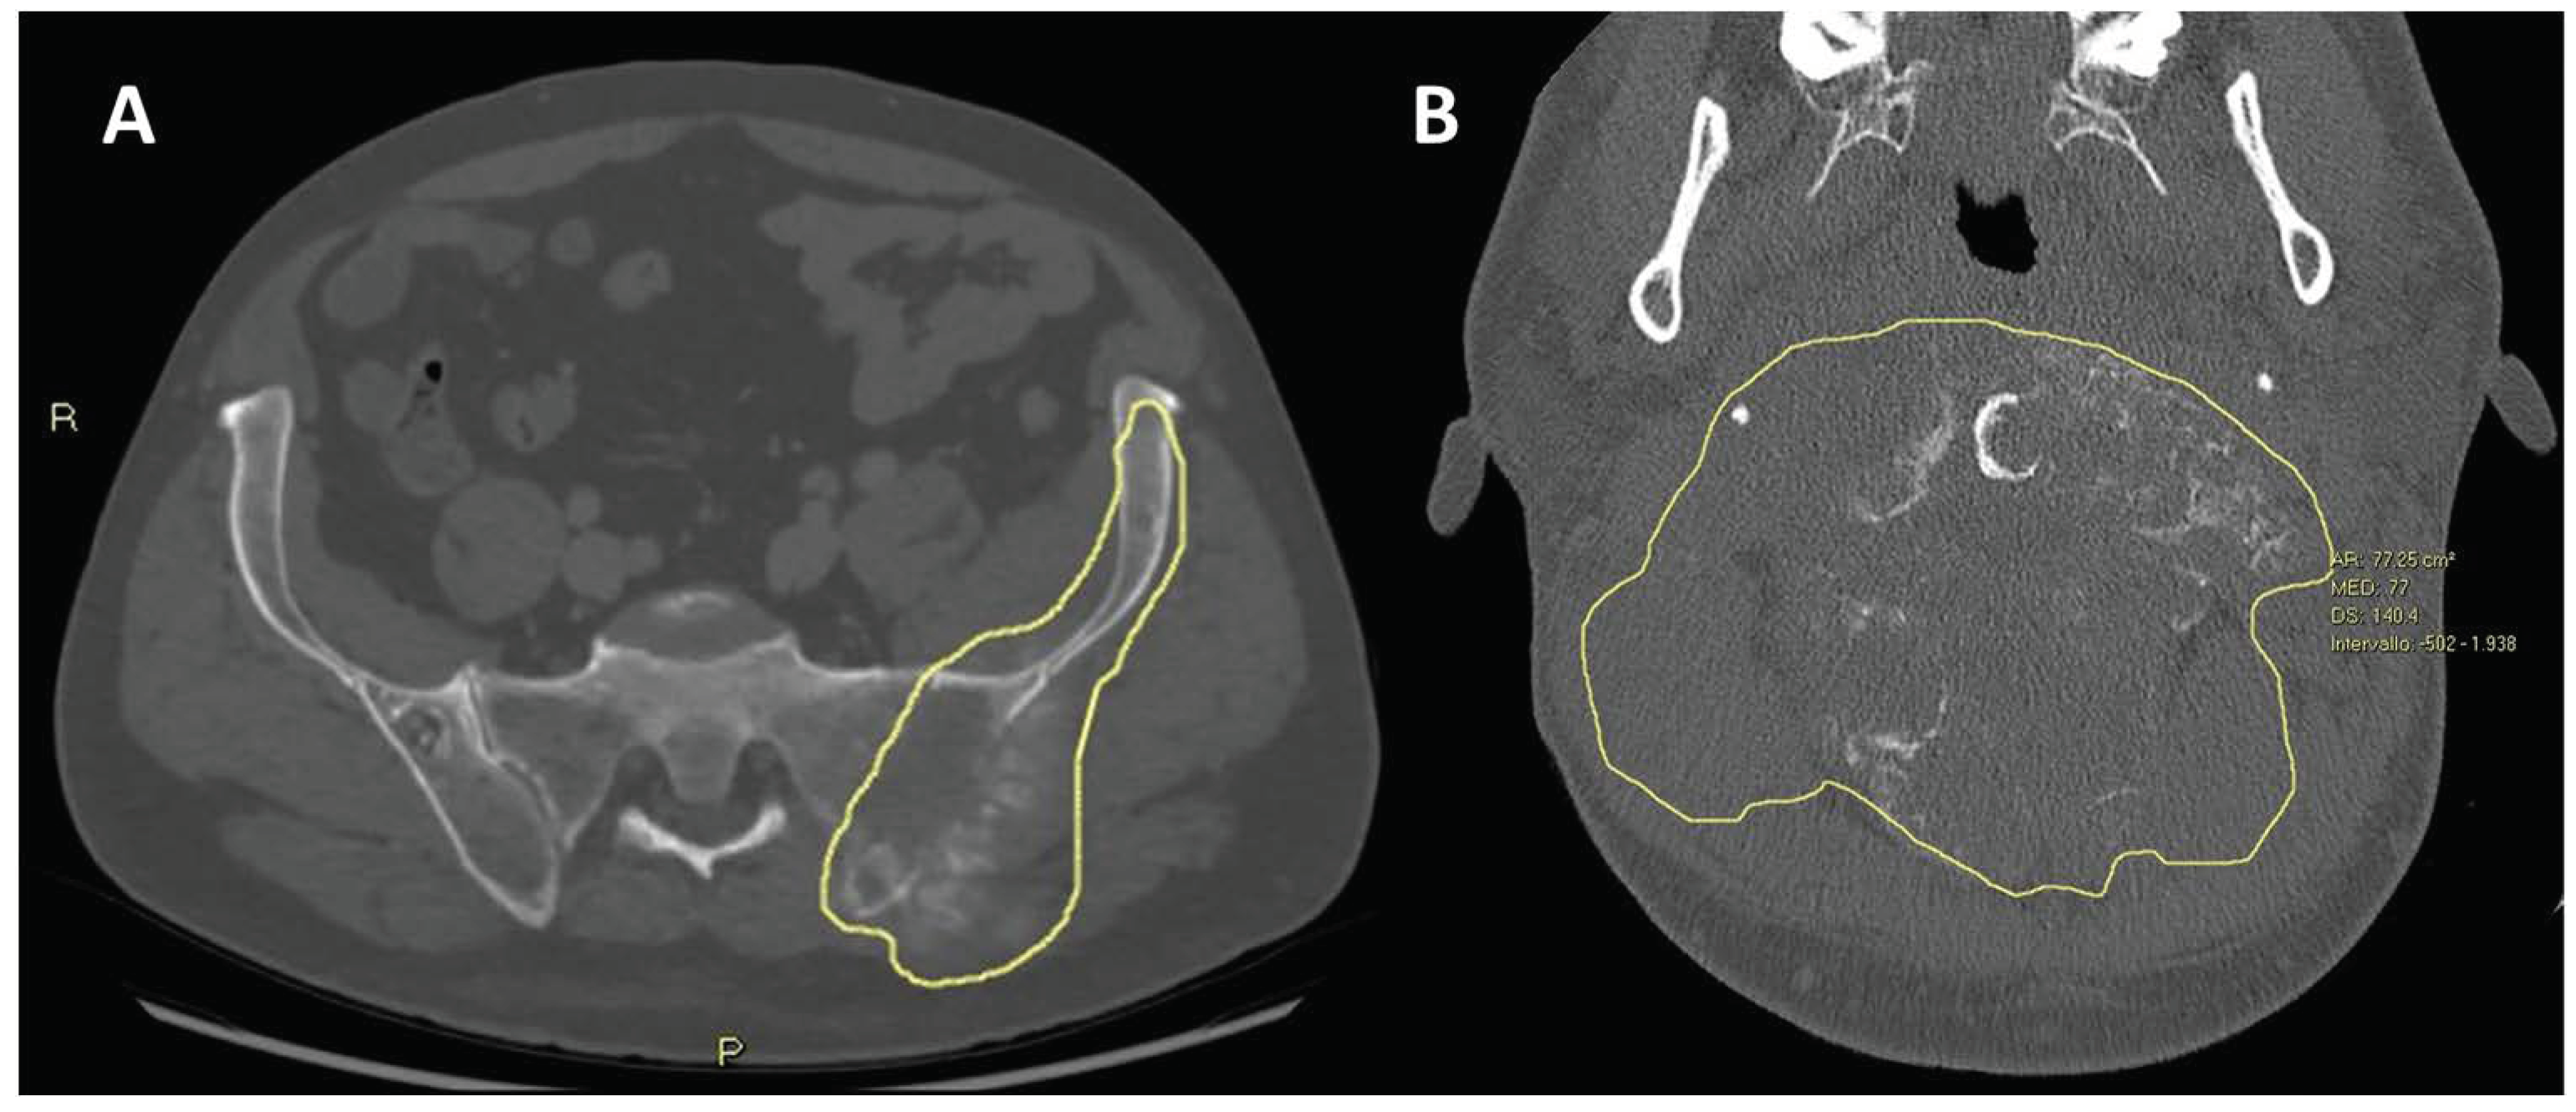

| - Large tumor size and volume (longest diameter > 7–10 cm, volume > 150 mL, volume >1/3 of involved bone) - Increased tumor volume and diameter during NACT | - Lower response rate to NACT - Decreased OS and EFS |